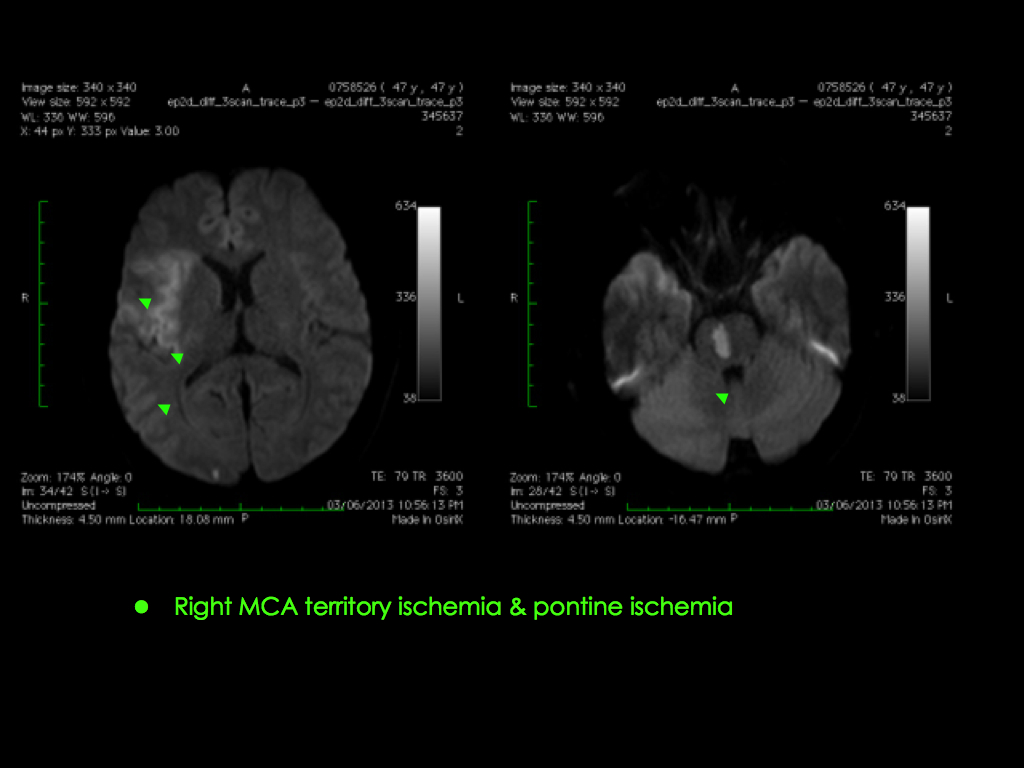

Sometimes if there is an underlying diseased and narrowed brain artery that is causing the stroke, our Stroke Neurosurgeons will implant a soft metallic stent for reconstructing the brain artery.